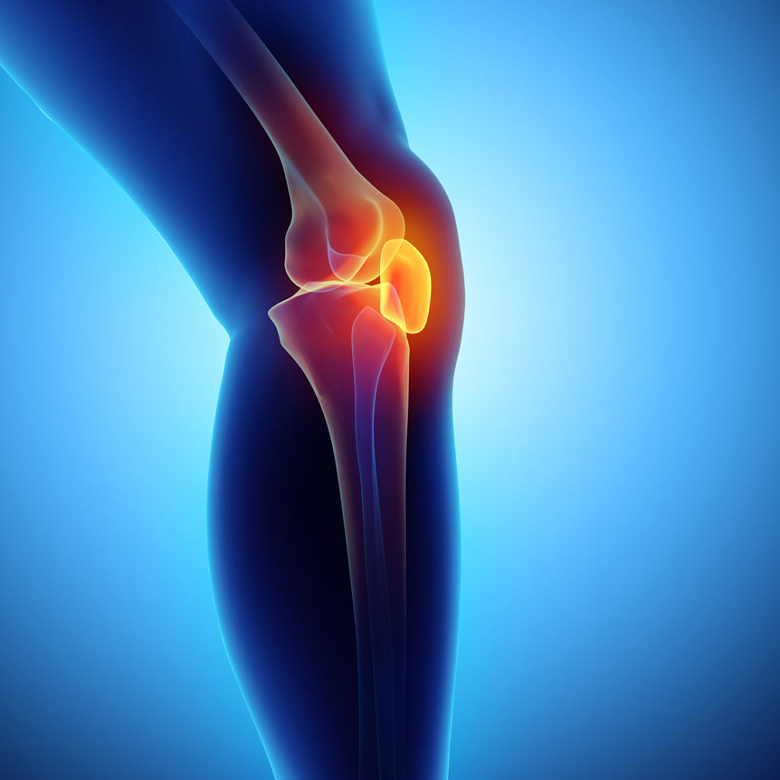

These days, these are the most common complaints. We provide ABHYANGAM massage therapy which is done with gentile warm ayurvedic oils for rejuvenation, relaxation, pain relief, etc.

Rheumatic diseases are a group of auto-immune connective disuse disorders. This treatment helps at reducing inflammation and symptoms like pain, swelling, etc,